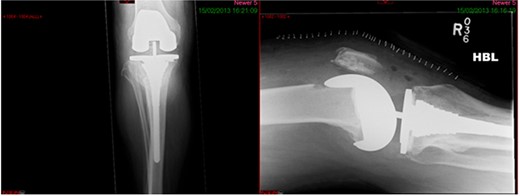

This case report follows a 67-year-old gentleman who sustained a Schatzker VI fracture of his right tibia after falling 2 m from a ladder (Fig. 6). The injury was closed and neurovascularly intact; he was managed initially in a neighbouring health board with a bridging external fixator because of the high degree of comminution. He was referred to the current institution; and at a routine review 3 weeks post-injury, it was noted that a pin had fractured. The external fixator was removed, and he was converted into an above knee cast. He progressed to a Sarmiento cast and then a range of motion brace at 12 weeks. Partial weight bearing was permitted, and he received physiotherapy. He was kept under regular review and the fracture had united (Fig. 7); he was noted to have a range of movement of 10°–60° with healed pin site wounds. At 8 months post-injury, he underwent total knee arthroplasty utilizing a posterior stabilised Depuy Synthes (Warsaw, In) Attune revision tibial metaphyseal sleeve and stem, and femoral component without sleeve or stem. The patient had an uncomplicated recovery and kept under routine review in the outpatient clinic. At 6 months’ review, the patient had a range of motion of 0°–105°, fully healed wound and reported a significant improvement in pain. The patient used no walking aids, and the Oxford Knee score was 40 (Fig. 8).